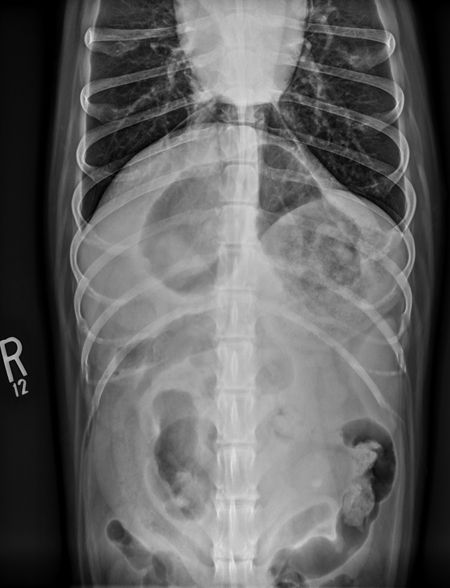

Figure 1C: Ventrodorsal view.

Figure 2A: This radiograph was obtained six hours after barium administration. Note all the barium is within the colon, except for a focal region in the stomach. This was a gastric foreign body (Vetrap) that was retained in the stomach.

Figure 2B: Ventrodorsal view.